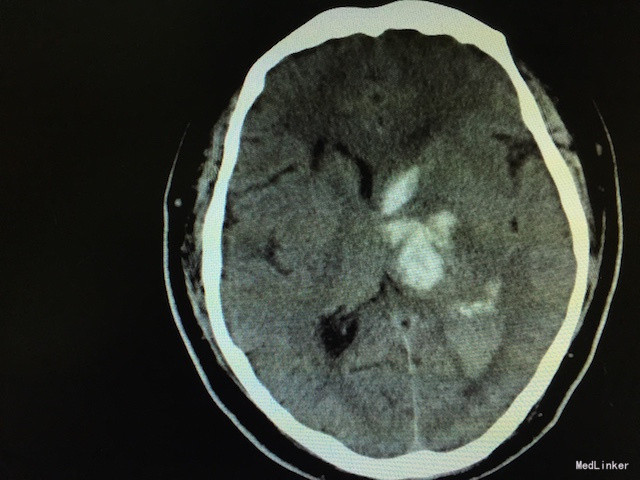

查体:右侧“三偏征”明显(偏瘫、偏身感觉障碍、偏盲),右病理征可疑阳性。 辅助检查:急诊行头颅CT,如下图,左侧基底节区出血。

诊断:脑出血 高血压3级(极高危) 治疗:安静卧床、脱水降颅压、冰帽降低脑组织代谢、调整血压、止血治疗等。